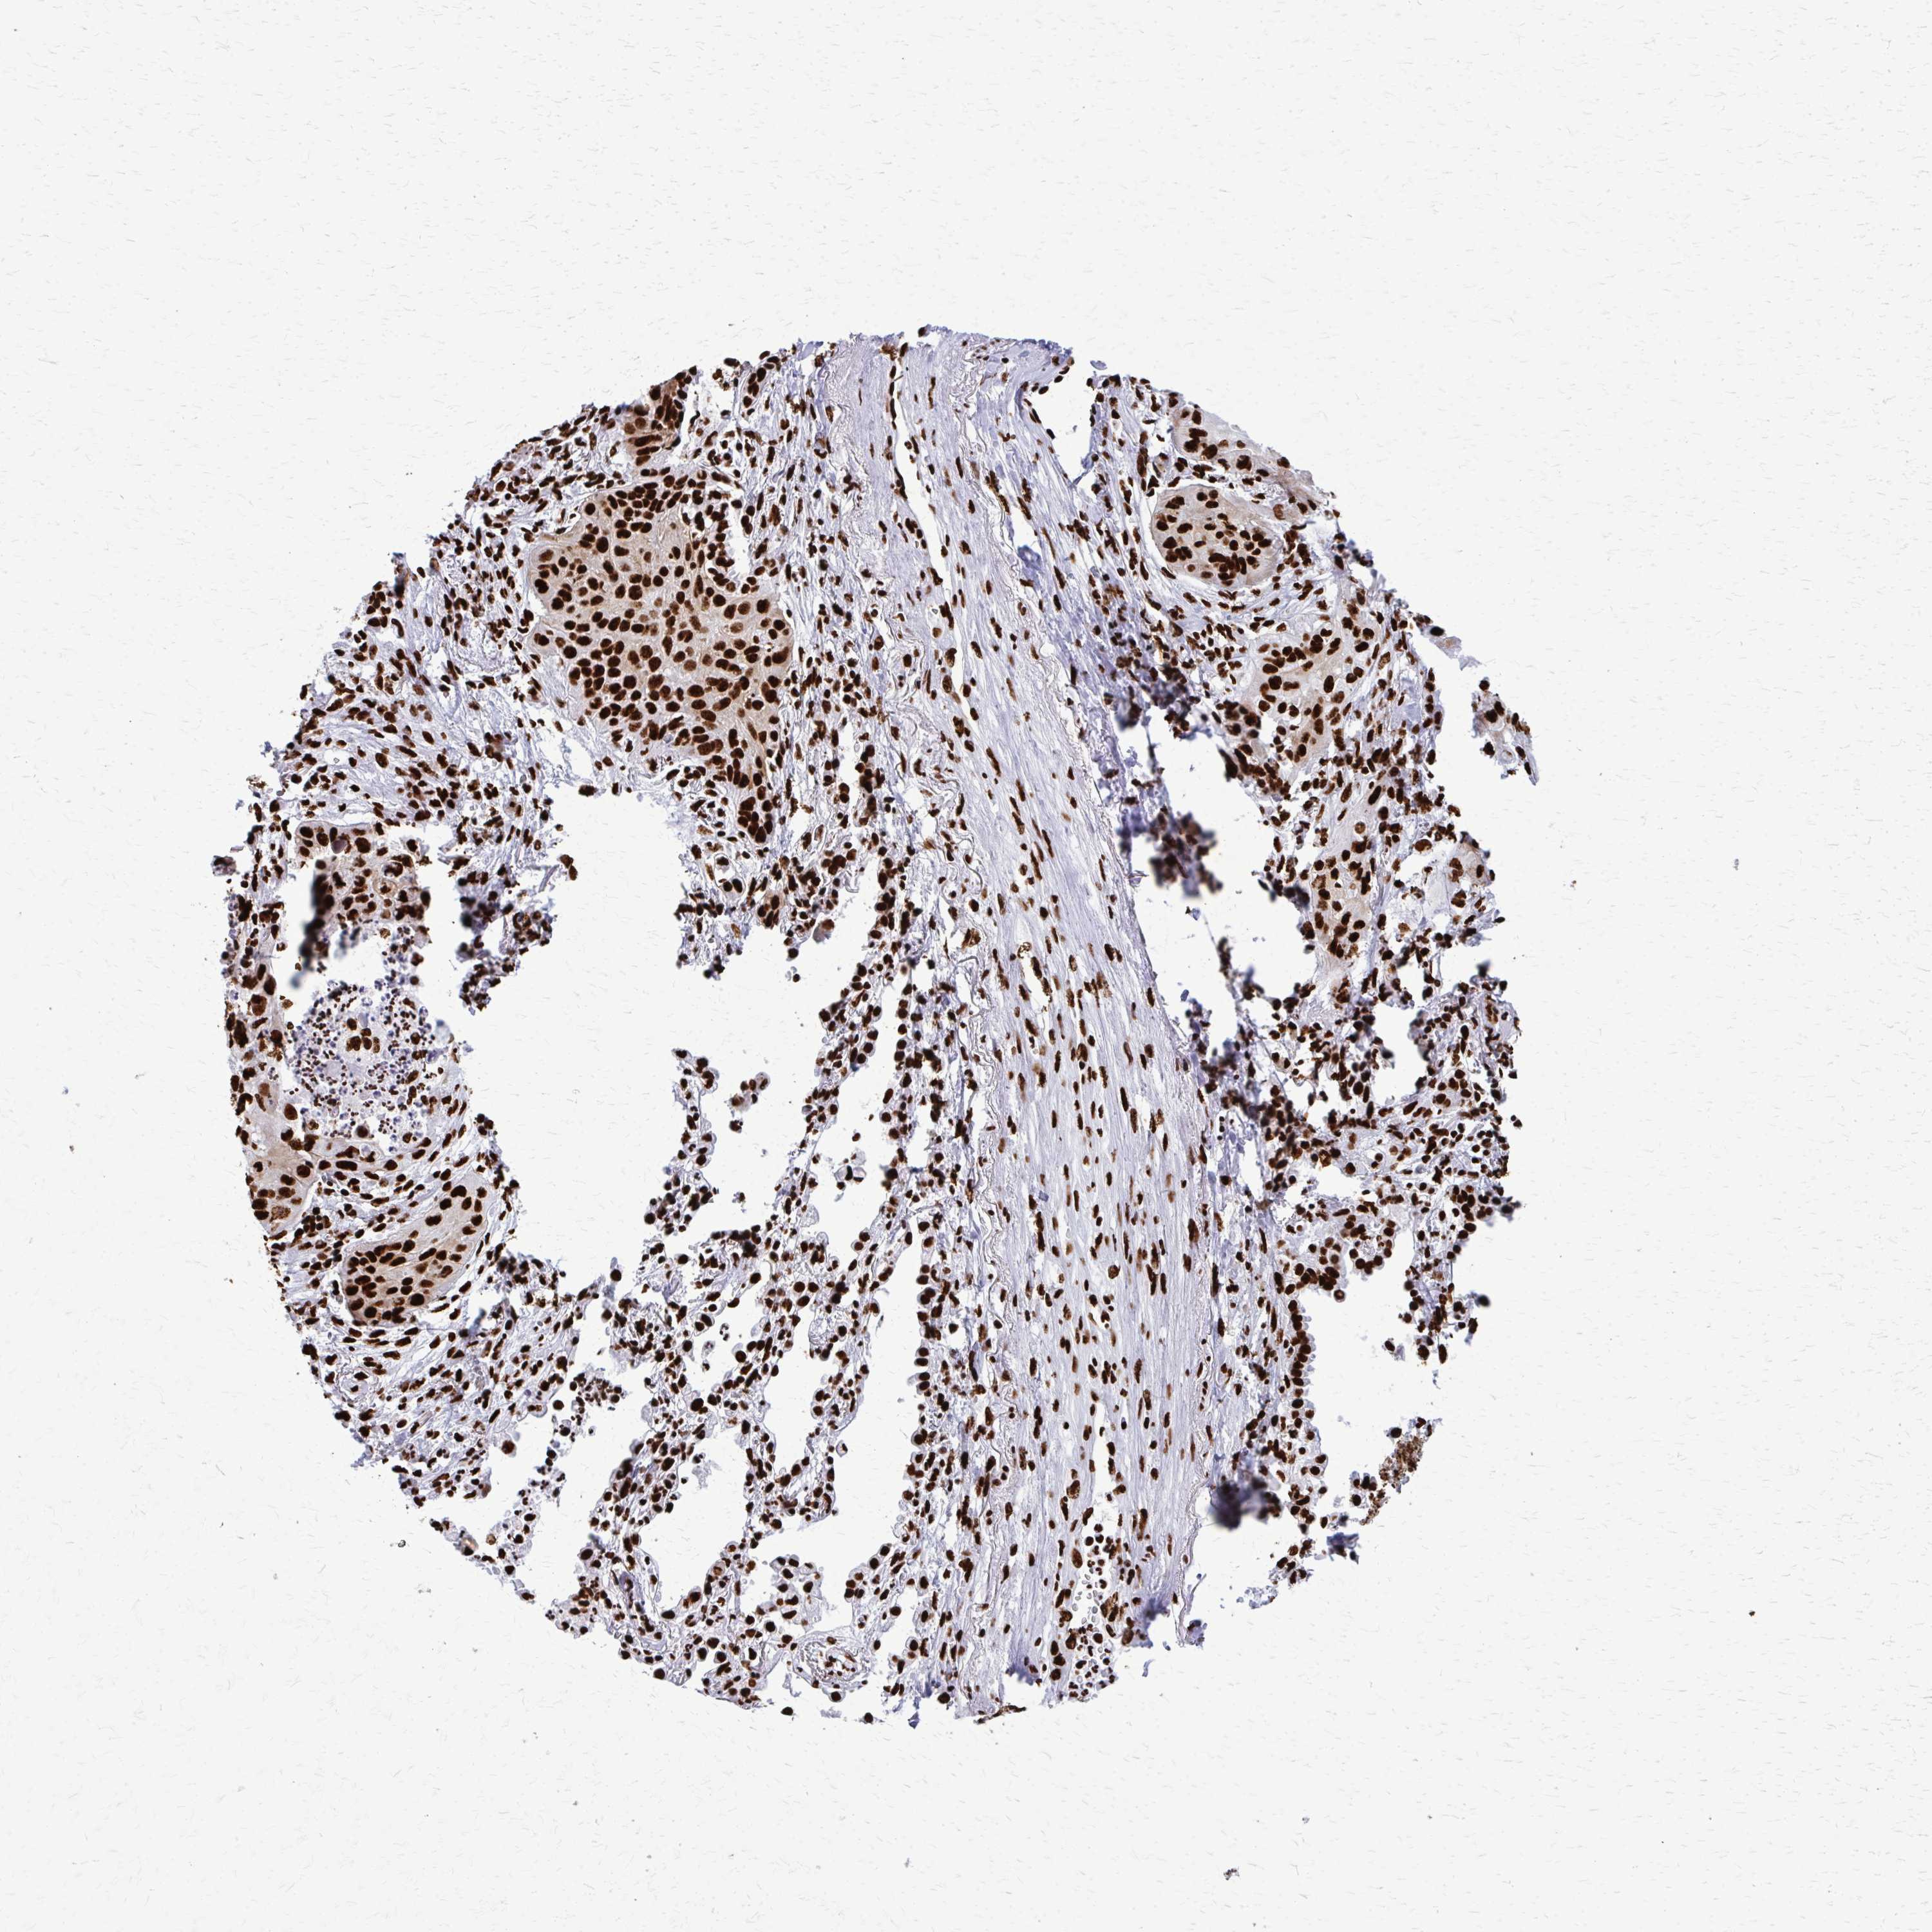

CANCER LUNG CANCER Show tissue menu

LUAD TCGA LUAD VALIDATION LUSC TCGA LUSC VALIDATION PROTEIN LUAD CPTAC PROTEIN LUSC CPTAC PROTEIN EXPRESSION